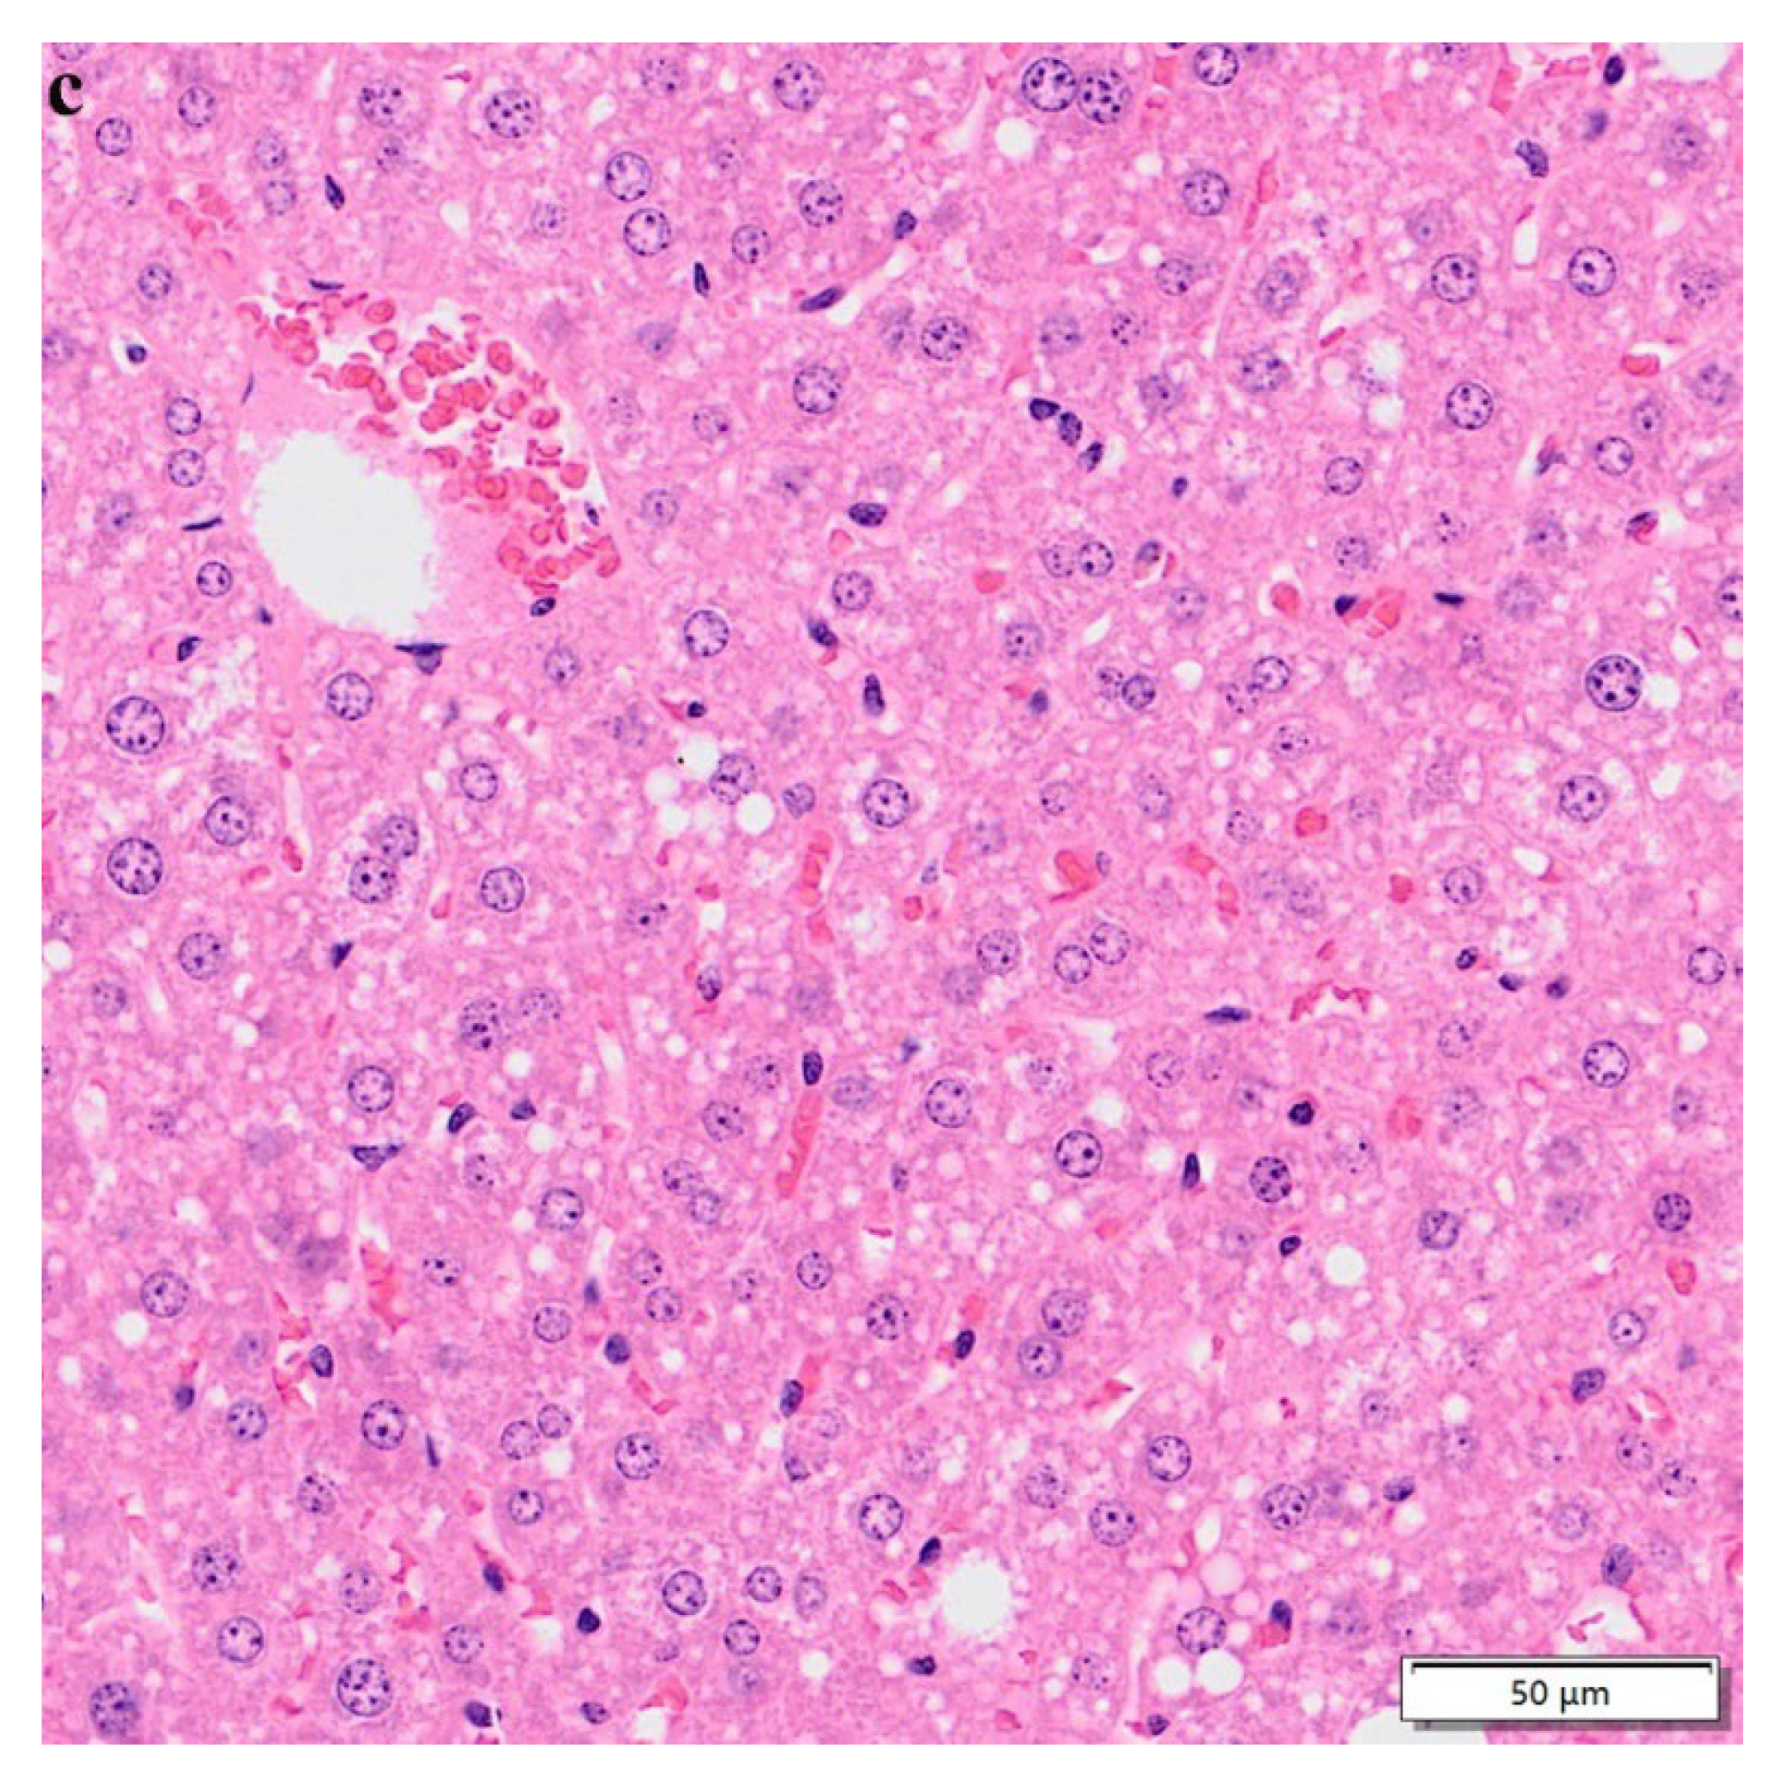

3.7. Hematoxylin–Eosin Staining